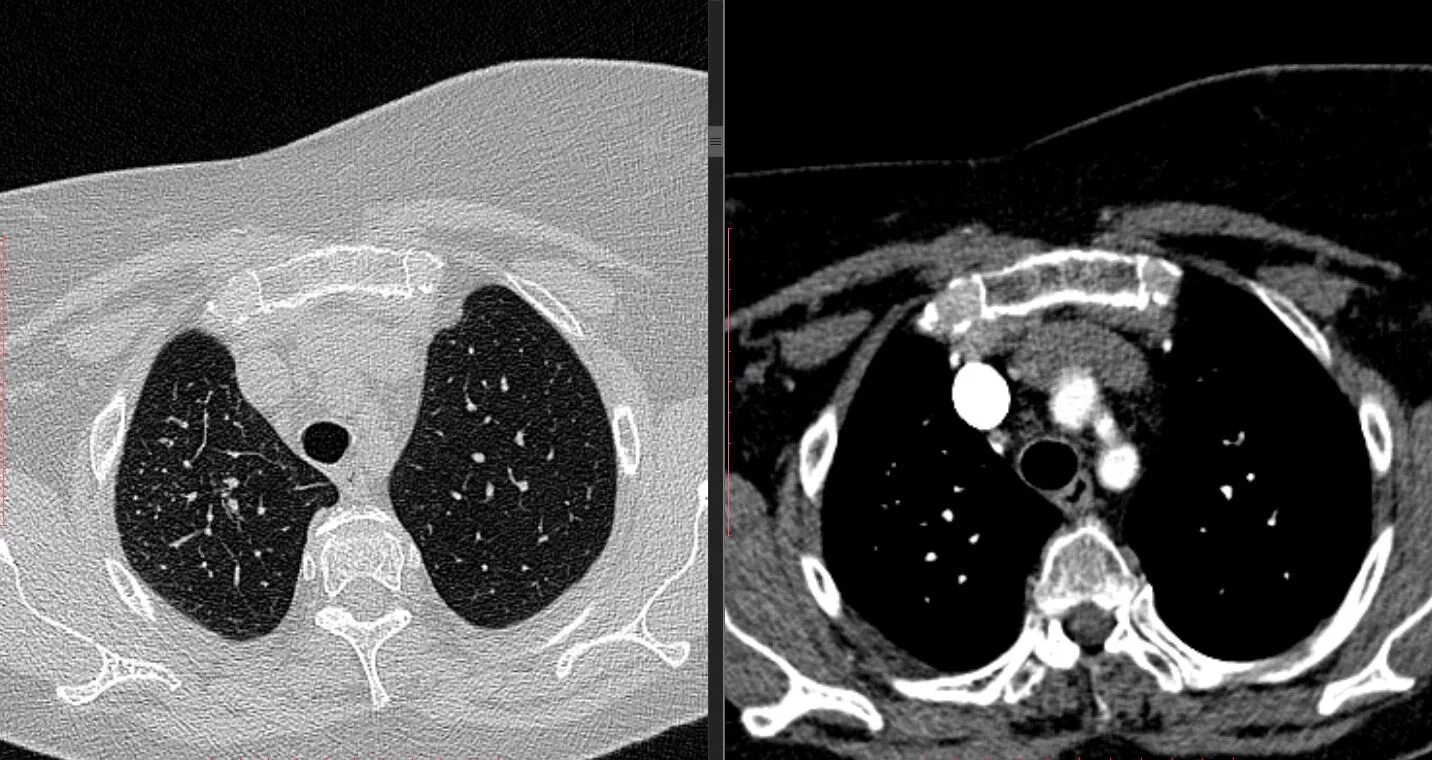

Как на кт выглядит рак